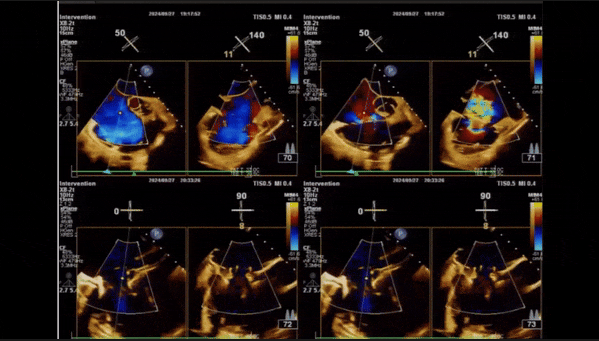

術后即刻返流

術中經食道超聲輔助下可見LuX-Valve Plus夾持件抓捕瓣葉狀態良好,夾持件在位,室間隔錨定位置良好,假體瓣膜整體錨定狀態穩固。

術后即刻經食道超聲可見,三尖瓣假體瓣膜位置合適,牛心包瓣葉運動狀態良好,開閉正常,瓣周及瓣葉對合緣處未見明顯返流,心電圖及心包狀態較術前無明顯變化。

術前術后返流情況對比